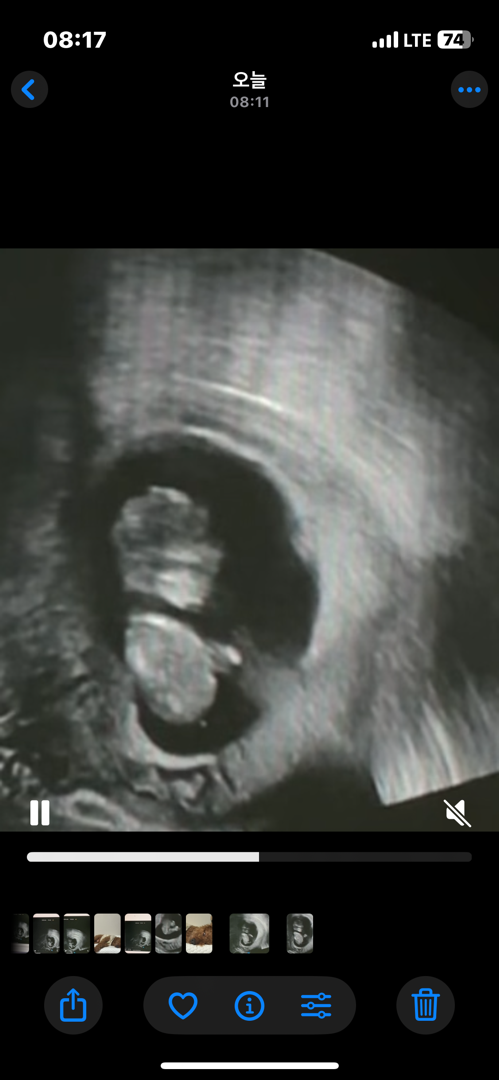

11주차 이지만 넘 궁굼해요!!!

희미하지만 딸일까요 아들일까요 ㅎㅎ